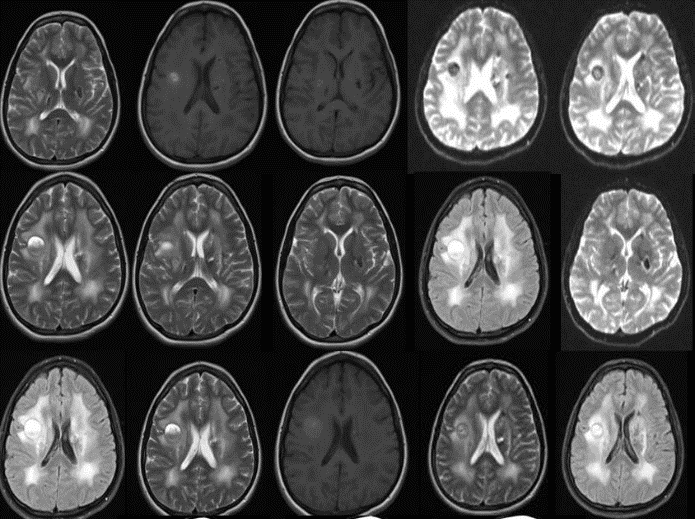

T1-weighted MR imaging revealed an approximately 16 mm diameter hyperintense lesion with circumferential calcification and gadolinium administration T2-weighted MR imaging showed a central focal milimetric contrast containing hyperintense lesion in the right corona radiata. Bilateral centrum semiovale white matter are heterogenic. After gadolinium administration, left centrum semiovale showed a focal contras containing area. Also there is a intense edema around bilateral centrum semiovale. This intense edema spread to the to corona radiata. The contrast magnetic resonance imaging (MRI) showed bilateral basal ganglion calcifications (Figure 1). An electroencephalogram (EEG) was normal. She was started on albendazol (800 mg/day).

Figure 1: MR imaging revealed an approximately 20 mm diameters lesion in the right frontoparietal area and 12 mm diameter lesion in adjacent to the left lateral ventricle.